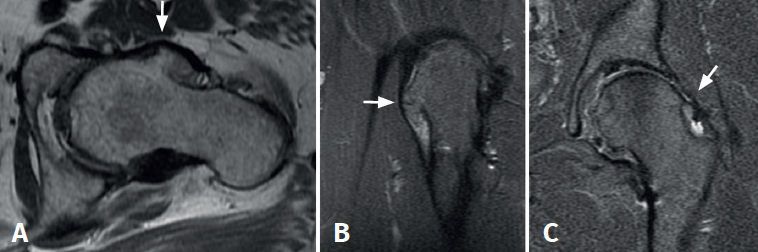

We present the case of a 49-year-old woman with left hip pain and limping for approximately two years. Her history indicated surgery of the hip in adolescence, though the cause of surgery was not known, and no documentation was available. The physical examination revealed pain in response to flexion and internal rotation of the hip, with positive anterior impingement manoeuvring. The plain X-rays (Figure 1) showed large, isolated exostosis in the femoral head-neck transition zone, with no evidence of associated exophytic lesions. The magnetic resonance imaging study revealed exostosis of the anterolateral surface of the femoral neck, measuring 21 × 14 mm in diameter (Figure 2), with signs suggestive of rupture of the anterosuperior labrum.